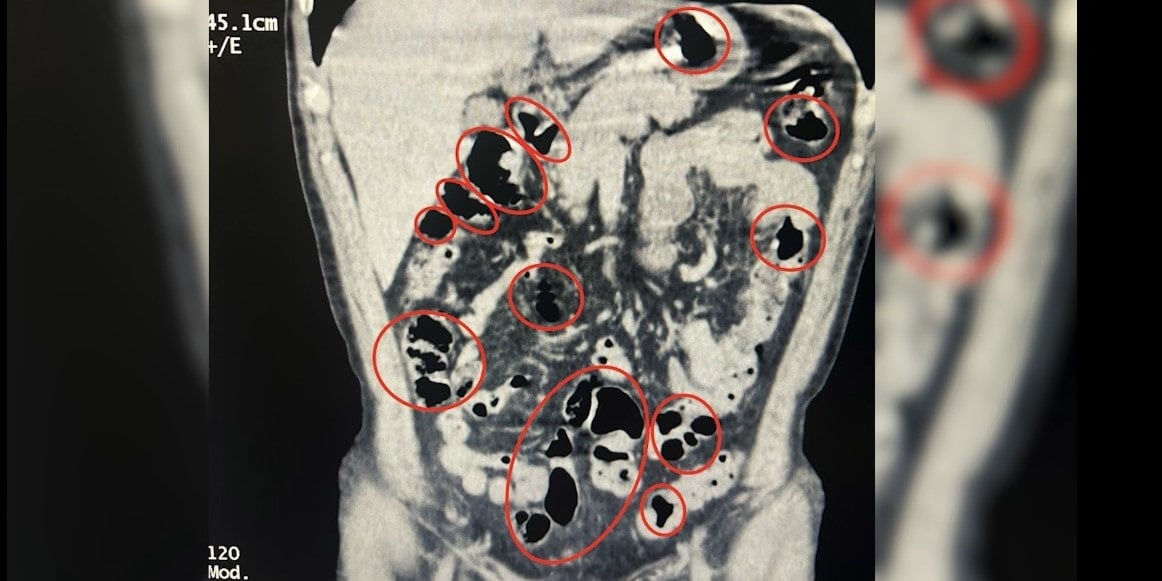

Tatvan Devlet Hastanesi’ne götürülen şüphelilerin röntgen ve tomografi görüntülerinde mide ve bağırsaklarında da yabancı maddeler tespit edildi. Yapılan tıbbi müdahale ile şüphelilerin yuttuğu 14 kapsül daha çıkarıldı. Böylece toplam 50 kapsül içinde 385 gram metamfetamin ele geçirildi.